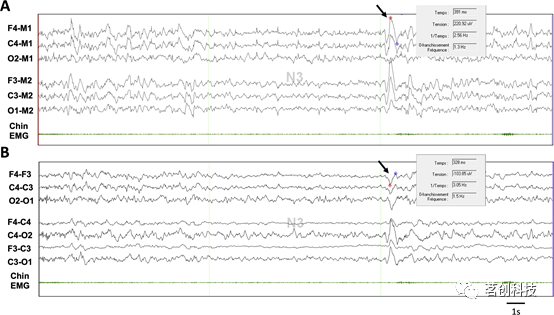

众所周知,脑电图所包含的信息远远超过了评分规则中使用的信息。然而,对这些信息的利用取决于评分者和记录特性(包括蒙太奇、采样率和滤波器的设置)。评分规则是针对电极数量较少(F4-M1、C4-M1、O2-M1)的特定蒙太奇设计的,并且某些特征的优先地形和特定振幅(例如慢波的75μV峰-峰振幅)在很大程度上取决于这种蒙太奇(图2)。在实践中,使用多种EEG蒙太奇,如果最终评分结果不受AASM EEG蒙太奇的显著影响,那么可用电极数量越多,评分者之间的一致性越好,并且可能会导致睡眠分期和觉醒检测的变化。

图2.不同EEG蒙太奇的慢波峰-峰振幅。